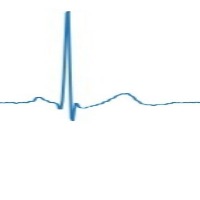

Couplet Computer Vision Project

Cardiac Monitoring: Couplet can be incorporated into patient monitoring systems to detect the various types of couplets in real-time, allowing healthcare professionals to identify arrhythmias and other cardiac anomalies. Early intervention can lead to better patient outcomes.

Telemedicine: Couplet can be integrated into telemedicine platforms to remotely assess a patient's electrocardiogram (ECG) signals. This helps improve access to care for patients who live in rural or hard-to-reach areas, allowing physicians to review their ECG and determine if there are any issues that require immediate attention.

Wearable Device Analysis: Couplet can be embedded into wearable health devices, such as smartwatches or fitness trackers, to analyze ECG data in real-time. This can help users monitor their heart health and alert them to any abnormalities, encouraging proactive healthcare management.

Medical Research: Couplet can be used by researchers studying the prevalence and causes of various couplet types. Automating the identification process can save time and improve accuracy, allowing researchers to focus on understanding the underlying mechanisms and developing effective treatments.

Medical Training and Education: Couplet can be applied to educational materials and training modules, helping medical students and professionals learn to identify different couplet types. By automating the recognition process, trainees can test their skills and gain confidence in their ability to diagnose conditions related to couplet classes.